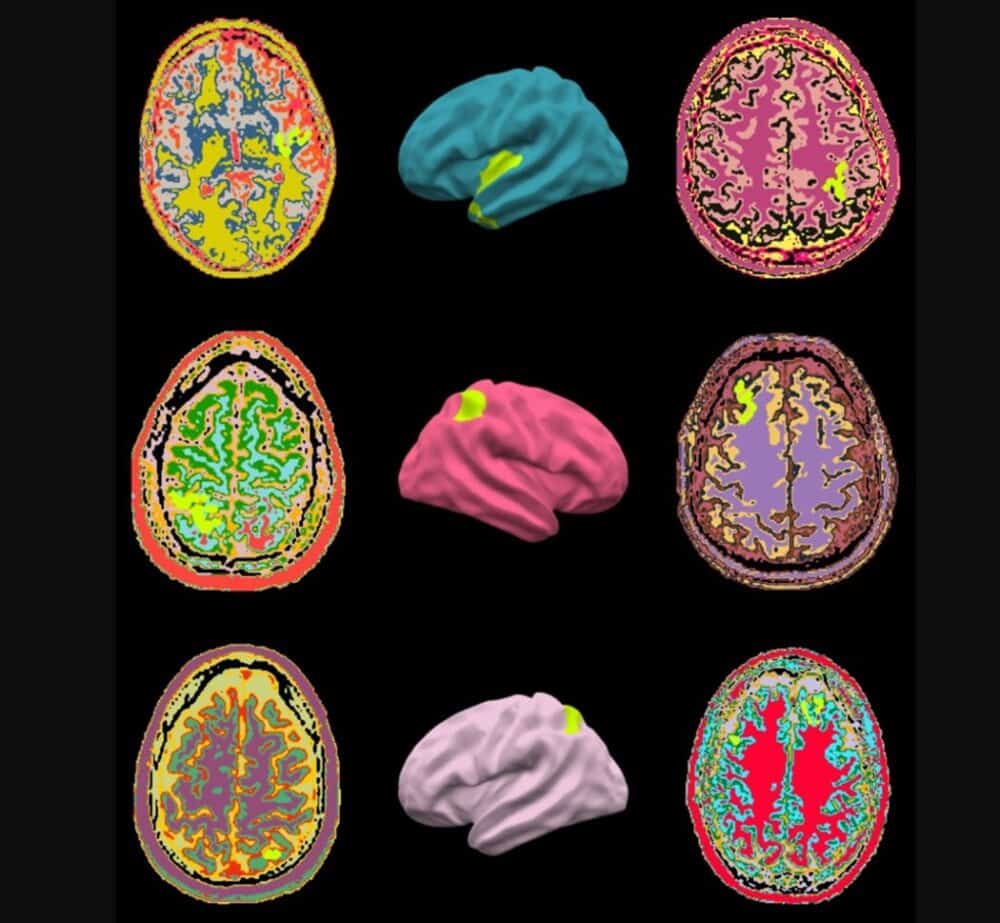

The scientists then analyzed features from all these MRI scans—such as how thick or folded the brain surface was—and measured them at around 300,000 locations in each subject’s brain. Expert radiologists from their team then labeled areas on the MRI scans as either being healthy or abnormal, and that enabled the team to train the algorithm to recognize patterns of features that characterize this particular FCD brain abnormality.

So, the MELD Project added additional features so that the AI conclusions could be more easily understood by calculating which features contributed most to the final prediction. In other words, the information used by the algorithm to reach its conclusion is summarized into a supplementary report highlighting where and why in the brain the AI detected the abnormalities.

(Credit: MELD Project)